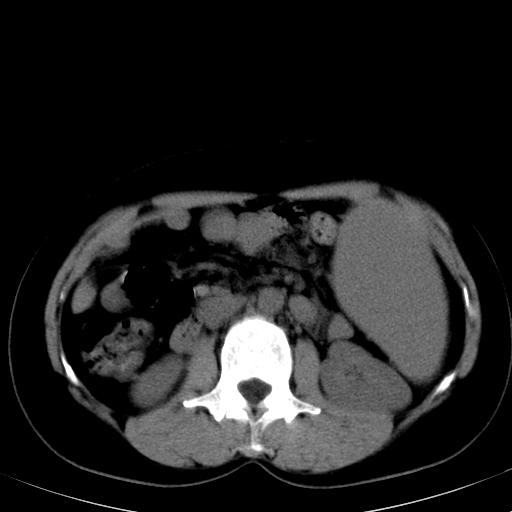

肝各叶比例失调,肝裂增宽,支持肝硬化\\脾大.

左肝大/右肝小,脾大,考虑肝硬化门脉高压,脾大。  不知是否有血吸虫感染病史

肝叶比例失调,肝左叶明显增大,包膜欠规整,脾大,支持考虑肝硬化、门脉高压、脾大。